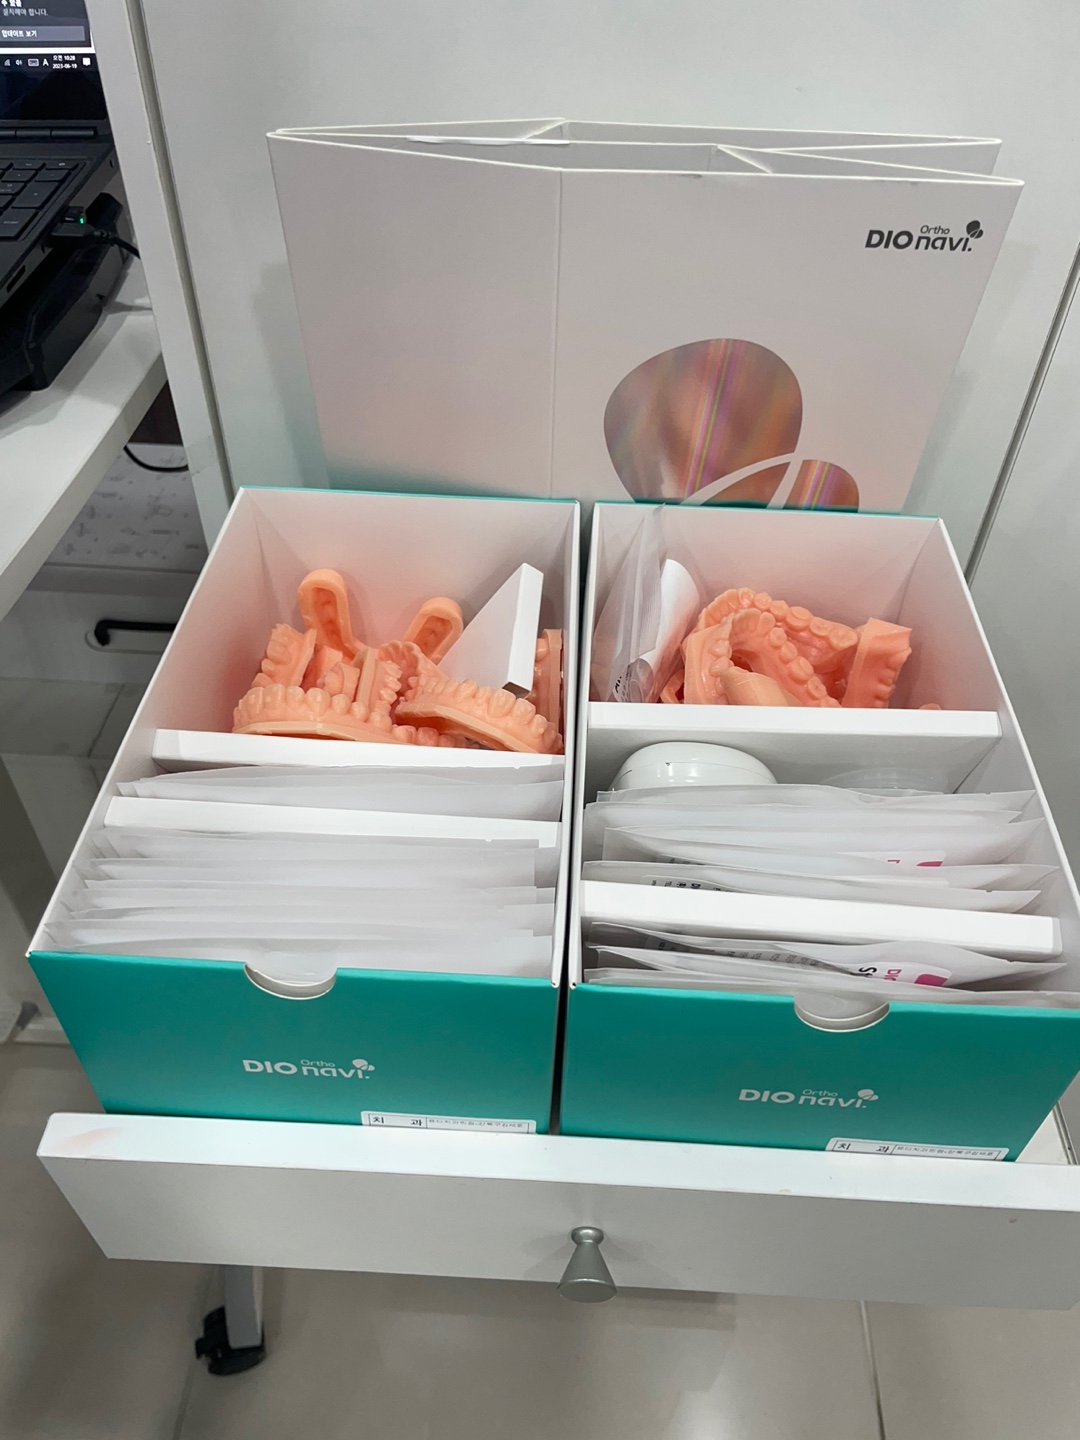

약 10일 뒤면 모든 장치들이 한꺼번에 만들어져서 본원에 오게 됩니다.

아래는 도착한 장치물입니다.